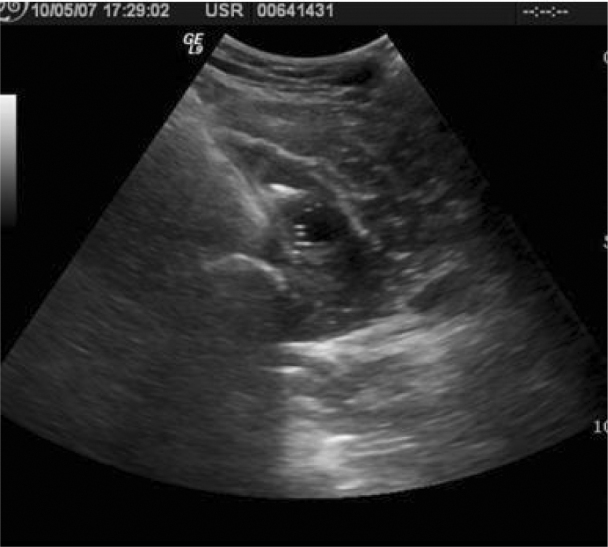

The overlying skin was marked at an appropriate level. The skin was cleansed with antiseptic solution and local lidocaine was infiltrated down to the margin of the abscess cavity. A Cook 18 gauge Turner needle was used to enter the abscess cavity and confirmed the loose body to lie dependent within the inferior medial aspect of the abscess as the loose body was readily movable (Fig. 4A). Under real-time ultrasound, blunt dissection was performed to enter the cavity with a Kelly clamp through the initial needle puncture site. The loose body was then grasped with the clamp and removed along the previously created tract (Fig. 4B). Post procedure scans were obtained and showed no residual loose body (Fig. 5). Hyperechoic foci within the region of hypoechoic fluid are representative of air that had been introduced into the abscess cavity during procedural manipulation. The skin was then re-cleansed for ultrasound guided abscess drainage.

Figure 5.

Post procedural transverse scan of the thigh shows hypoechoic fluid collection with absence of loose body.

To maintain sterility for fluid cultures, another Cook 18-gauge Turner needle was introduced into the fluid collection and aspiration of the fluid sample was obtained and sent for evaluation. Aspiration of approximately 55 cc of a purulent, thick fibrinous fluid was accomplished. A 10 Fr. Pigtail catheter was locked in place and connected to gravity drainage and a dressing was applied. Subsequent culture of the abscess fluid revealed Staphylococcus aureus. The patient was discharged on oral antibiotics and returned 10 days later for follow up. CT imaging revealed the abscess cavity to be markedly decreased in size compared to the prior study, measuring 1.4 × 1.0 × 1.0 cm (Fig. 5). The radio-opaque loose body seen previously within the fluid collection was no longer identified.